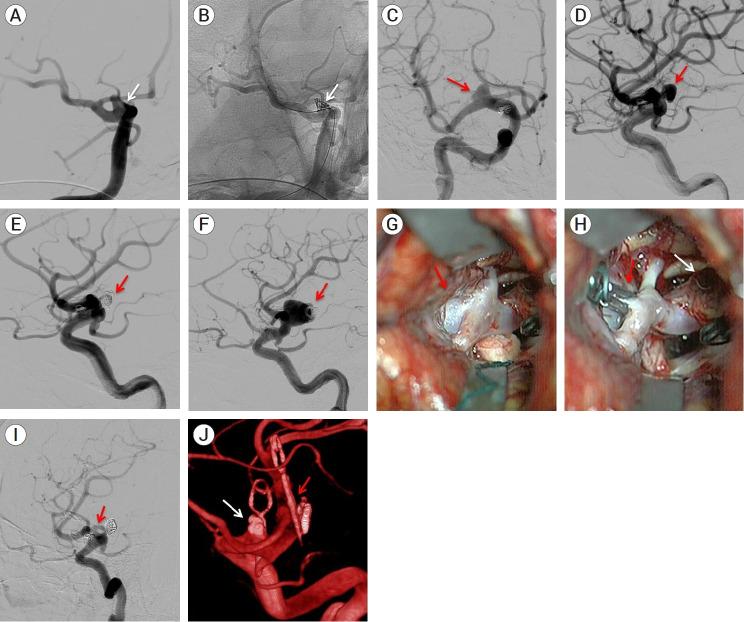

Retrospective analysis of nine (9) patients' data and final clinical/angiographic outcomes, who underwent surgical clipping of IAs in our center following initial endovascular treatment, over a 12-year period (2010-2022). Regarding the literature review, data were extracted from 48 studies including 969 patients with 976 aneurysms.

9 patients (5 males - 4 females) were included in the study with a mean age of 49 years. Subarachnoid hemorrhage was the initial presentation in 78% of patients. Aneurysms' most common location was the middle cerebral artery bifurcation (5/9) followed by the anterior communicating artery (3/9) and the internal carotid artery bifurcation (1/9). Indications for surgery were coil loosening, coil compaction, sac regrowth, and residual neck. Procedure-related morbidity and mortality were zero whereas complete aneurysm occlusion was achieved after surgical clipping in all cases (100%). All patients had minimal symptoms or were asymptomatic (mRS 0-1) at the final follow-up.

9例患者(5例男性 - 4例女性)纳入研究,平均年龄为49岁。78%的患者最初表现为蛛网膜下腔出血。动脉瘤最常见的位置是大脑中动脉分叉处(5/9),其次是前交通动脉(3/9)和颈内动脉分叉处(1/9)。手术指征为弹簧圈松动、弹簧圈压缩、瘤囊再生长和残余瘤颈。与手术相关的发病率和死亡率为零,所有病例(100%)在手术夹闭后均实现了动脉瘤完全闭塞。所有患者在最后一次随访时症状轻微或无症状(改良Rankin量表评分0 - 1分)。